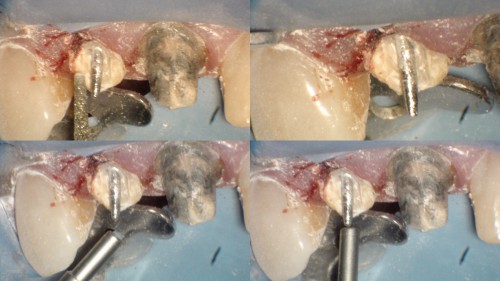

#5 Routine RCT

Deep sub-gingival margin. Always good to see a well isolated work space, which makes our […]